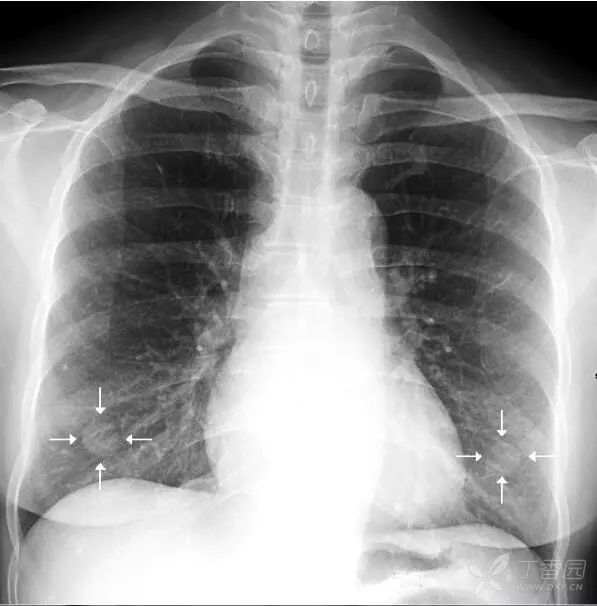

上图摄片时双上肢未充分内旋,导致双侧肩胛骨大部分重叠于双肺中上肺野中外带,导致相应肺野条带状密度增高。白色箭头标示右侧肩胛骨内侧缘,向肺外延续。左侧肩胛骨情况类似。